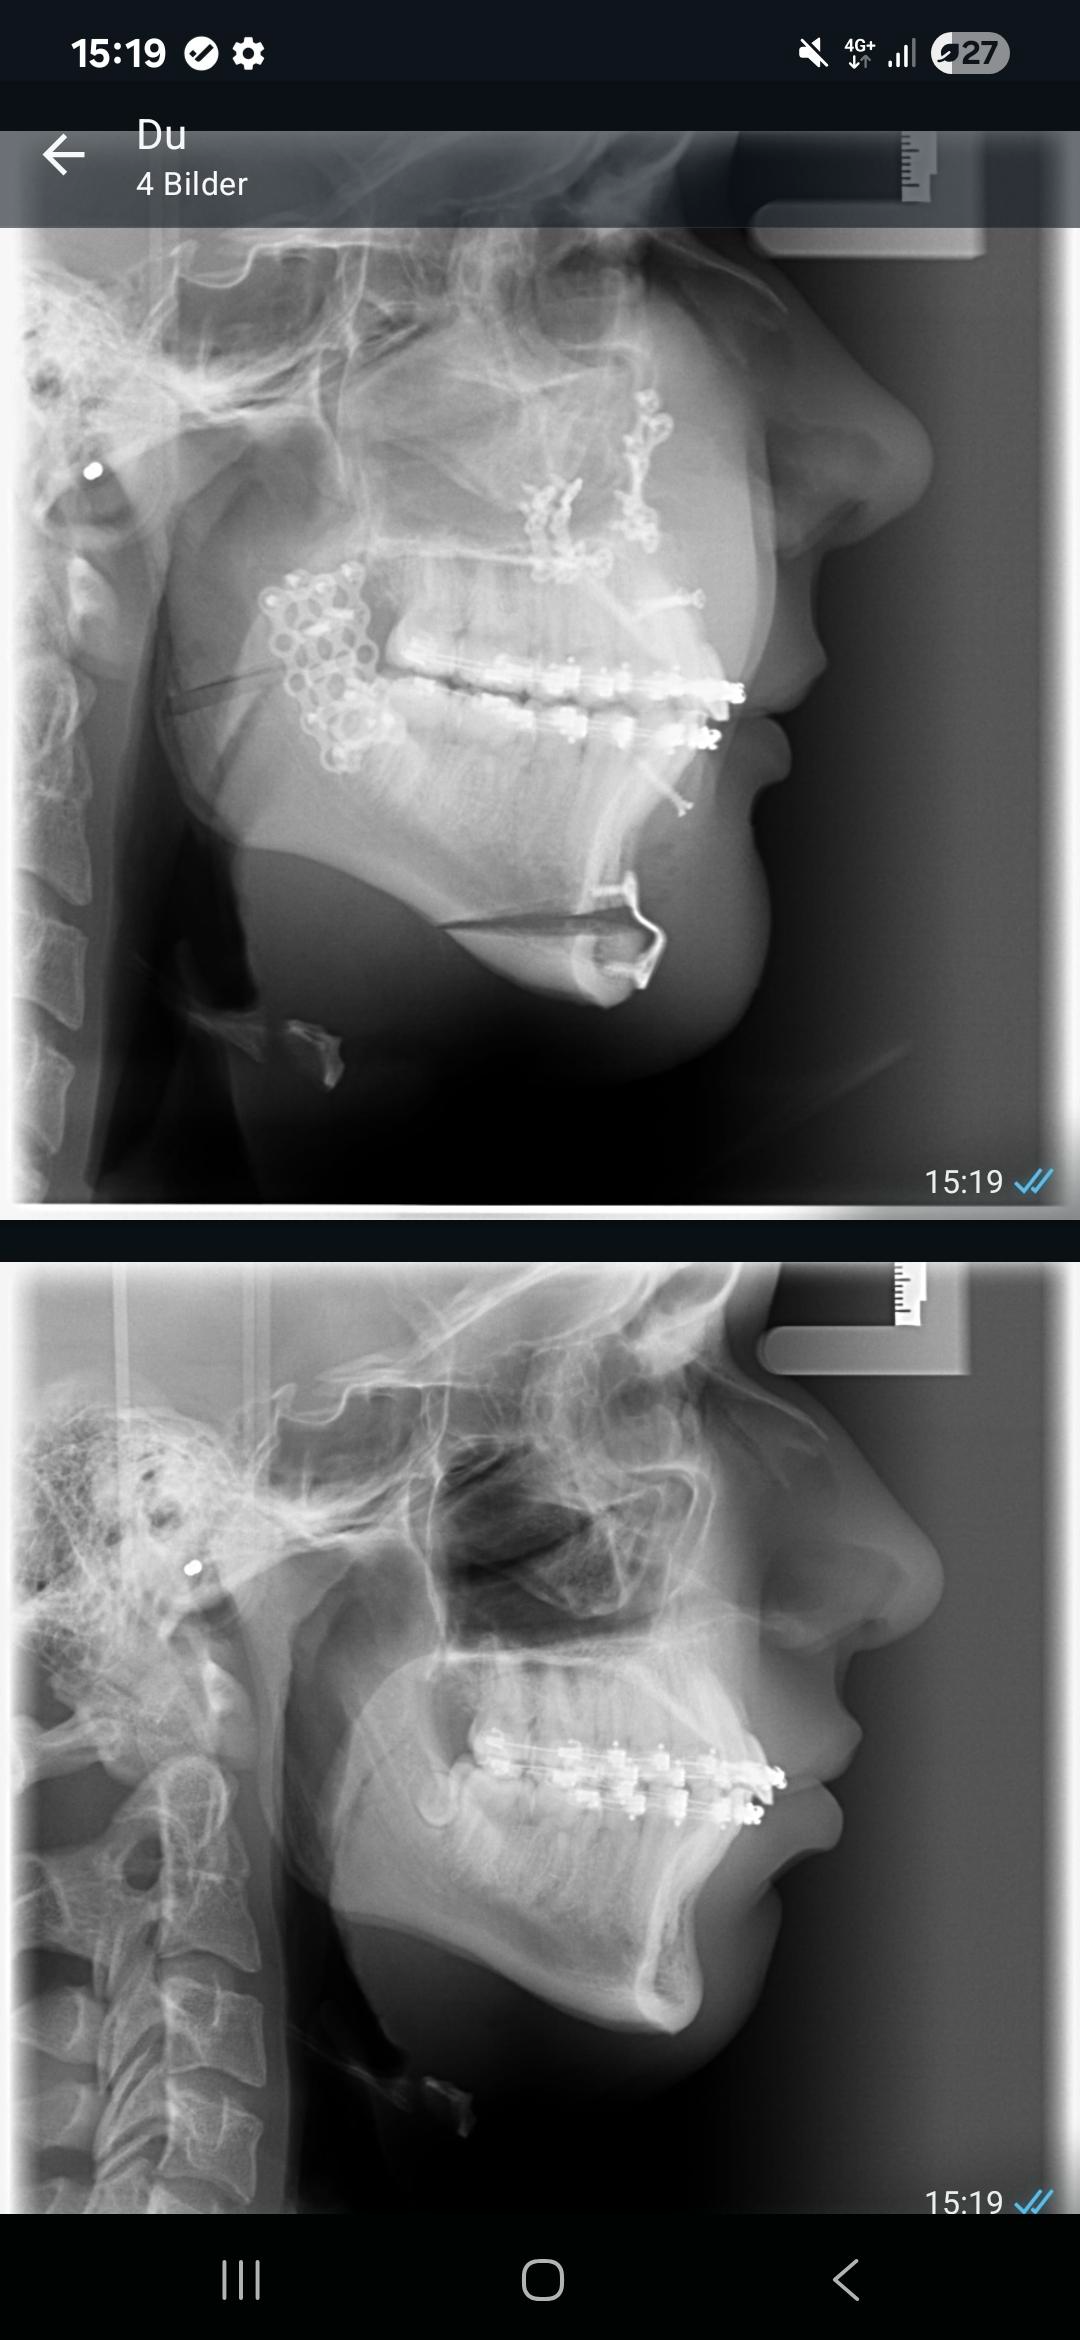

Do yall think it was worth it for 5k at 17 y/o?

Before:

After:

Before:

After: